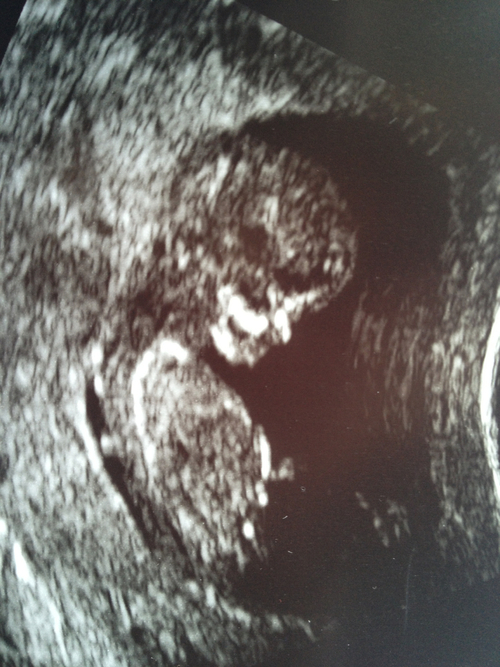

I'm new at this, but I am thinking girl. What do you guys think?

maybe girl but the nub isn't seen all that well